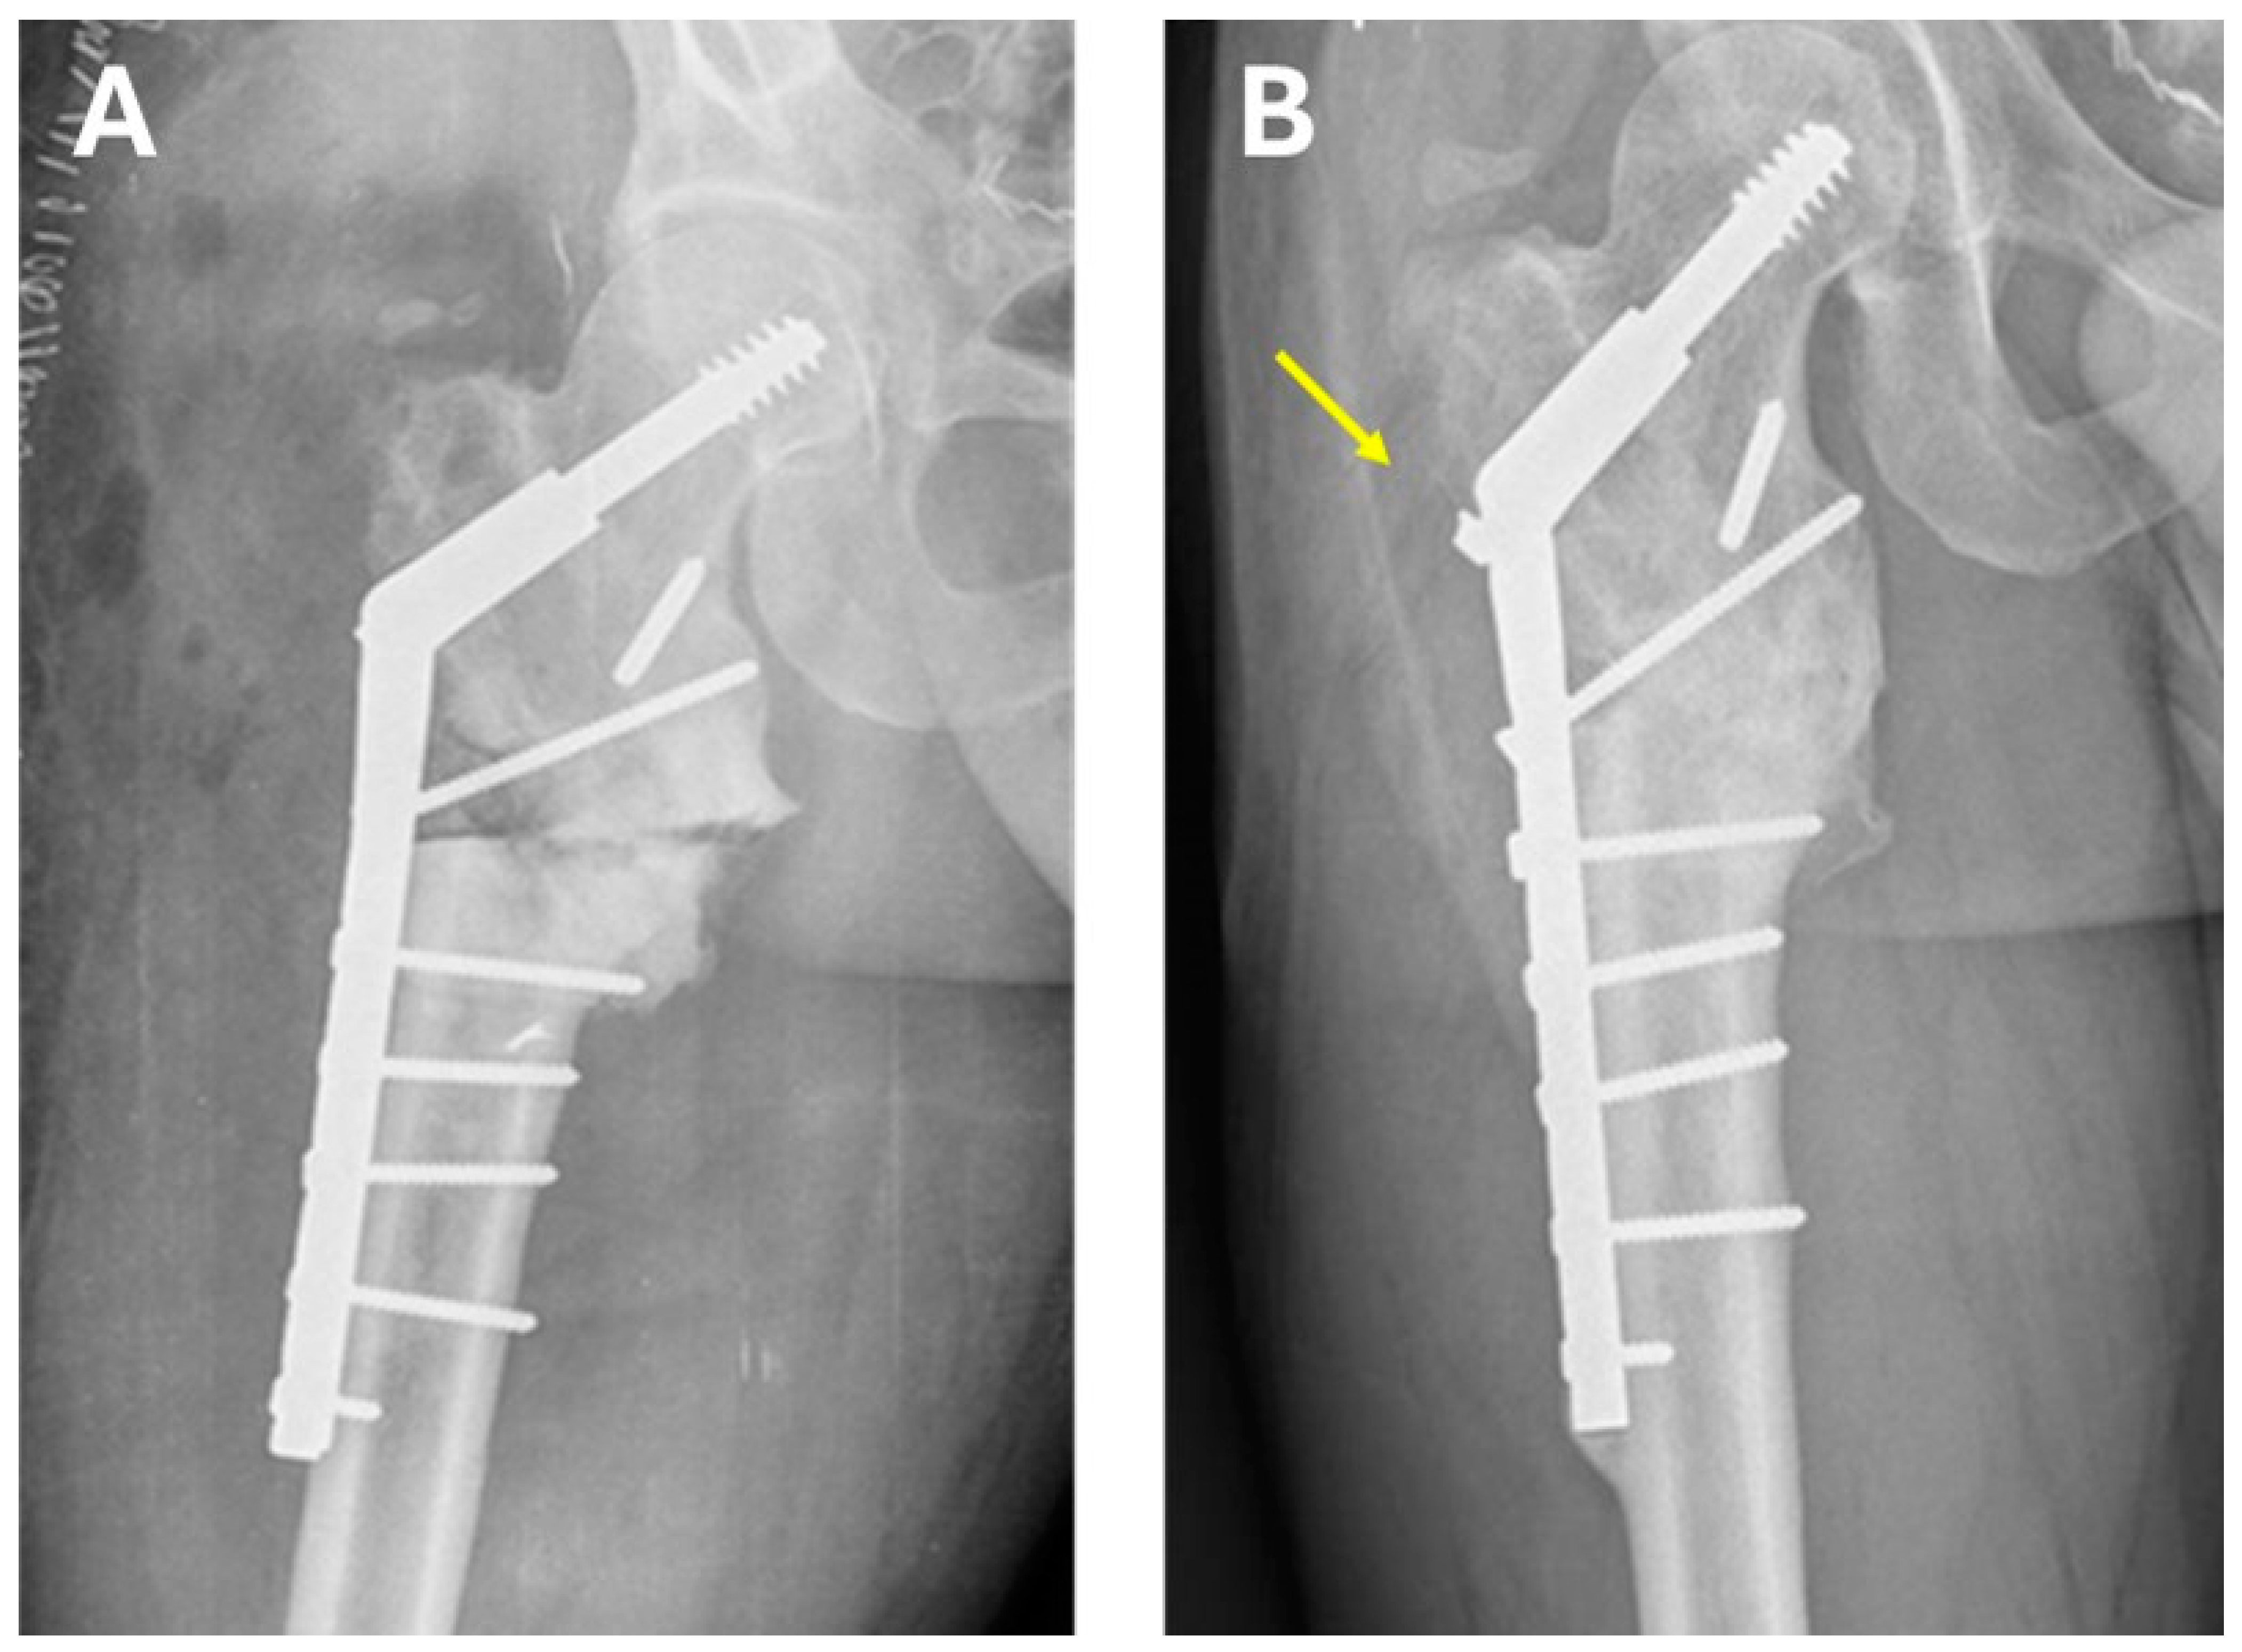

| Femoral neck angle post-surgery * | 142° | 150° | 150° | 147° | 145° | 146.8 (142–150) |

| Time to union (months) | 4 | 6 | 6 | 5 | 4 | 5 (4–6) |

| Harris Hip Score post-surgery * | 96 | 96 | 88 | 90 | 88 | 90 (88–96) |